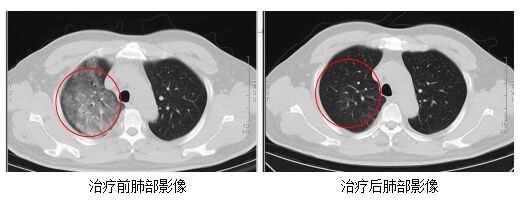

發(fā)熱門診醫(yī)生詳細(xì)詢問顧先生的既往病史,并為其進(jìn)行細(xì)致的體格檢查。胸部CT結(jié)果顯示,顧先生的雙肺存在大面積的炎癥病變。

在感染科醫(yī)護(hù)團(tuán)隊的精心治療與細(xì)致護(hù)理下,顧先生的發(fā)熱、咳嗽、胸悶等癥狀逐漸緩解。復(fù)查的CT結(jié)果顯示,肺部炎癥情況得到了明顯的改善。目前,顧先生已經(jīng)順利康復(fù)出院。